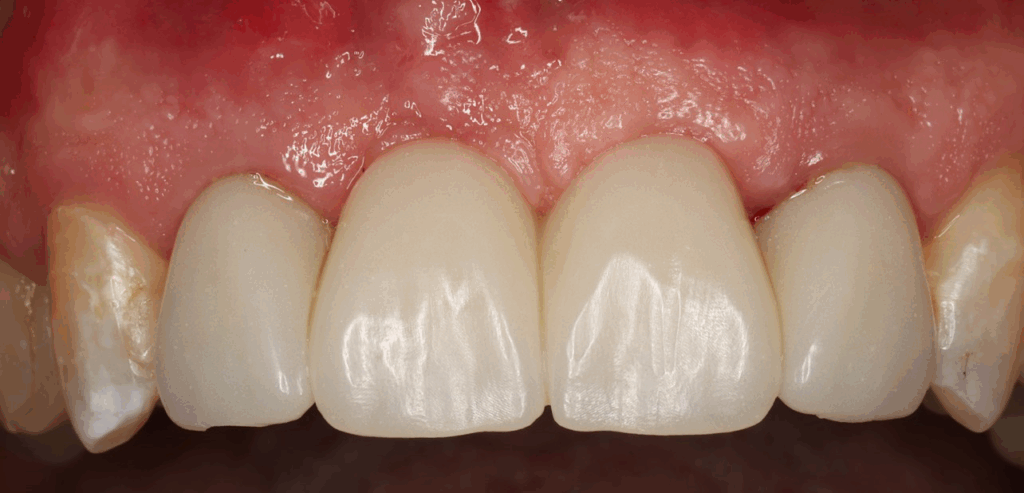

After 3 months of tissue training, patient returned for his final evaluation prior to final restoration.

Pt was ready to proceed with the final restorations and was referred back to his restoring doctor for his final bridge.